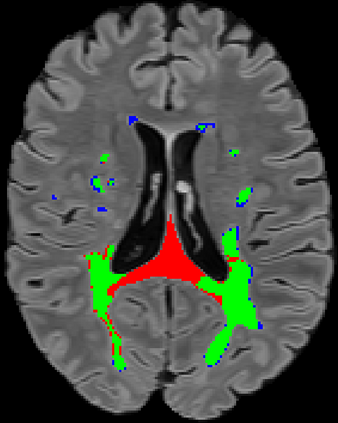

Recently, segmentation methods based on Convolutional Neural Networks (CNNs) showed promising performance in automatic Multiple Sclerosis (MS) lesions segmentation. These techniques have even outperformed human experts in controlled evaluation conditions such as Longitudinal MS Lesion Segmentation Challenge (ISBI Challenge). However state-of-the-art approaches trained to perform well on highly-controlled datasets fail to generalize on clinical data from unseen datasets. Instead of proposing another improvement of the segmentation accuracy, we propose a novel method robust to domain shift and performing well on unseen datasets, called DeepLesionBrain (DLB). This generalization property results from three main contributions. First, DLB is based on a large group of compact 3D CNNs. This spatially distributed strategy ensures a robust prediction despite the risk of generalization failure of some individual networks. Second, DLB includes a new image quality data augmentation to reduce dependency to training data specificity (e.g., acquisition protocol). Finally, to learn a more generalizable representation of MS lesions, we propose a hierarchical specialization learning (HSL). HSL is performed by pre-training a generic network over the whole brain, before using its weights as initialization to locally specialized networks. By this end, DLB learns both generic features extracted at global image level and specific features extracted at local image level. DLB generalization was validated in cross-dataset experiments on MSSEG'16, ISBI challenge, and in-house datasets. During experiments, DLB showed higher segmentation accuracy, better segmentation consistency and greater generalization performance compared to state-of-the-art methods. Therefore, DLB offers a robust framework well-suited for clinical practice.